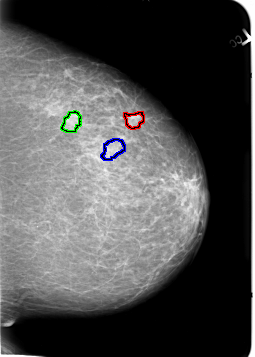

B_3021_1.LEFT_MLO

FILE: B_3021_1.LEFT_MLO.OVERLAY

TOTAL_ABNORMALITIES 3

ABNORMALITY 1

LESION_TYPE MASS SHAPE LOBULATED MARGINS CIRCUMSCRIBED-ILL_DEFINED

ASSESSMENT 3

SUBTLETY 3

PATHOLOGY MALIGNANT

TOTAL_OUTLINES 1

ABNORMALITY 2

ABNORMALITY 3